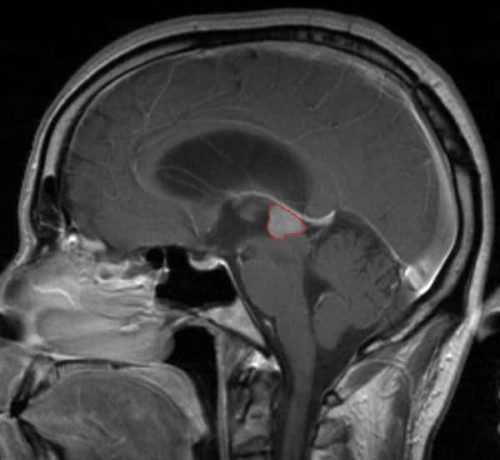

Диагностика образования с помощью МРТ

При применении МРТ специалисты могут выявить особенности структуры и состояния пораженной зоны, а также различить между собой доброкачественные и злокачественные образования. Важно отметить, что данная методика не использует ионизирующее излучение, что делает её безопасной для пациента.

Кроме того, МРТ позволяет осуществить динамическое наблюдение за изменениями, происходящими в клетках, что особенно актуально при долгосрочной терапии. На основе полученных изображений доктор может поставить точный диагноз и выбрать оптимальную стратегию лечения.